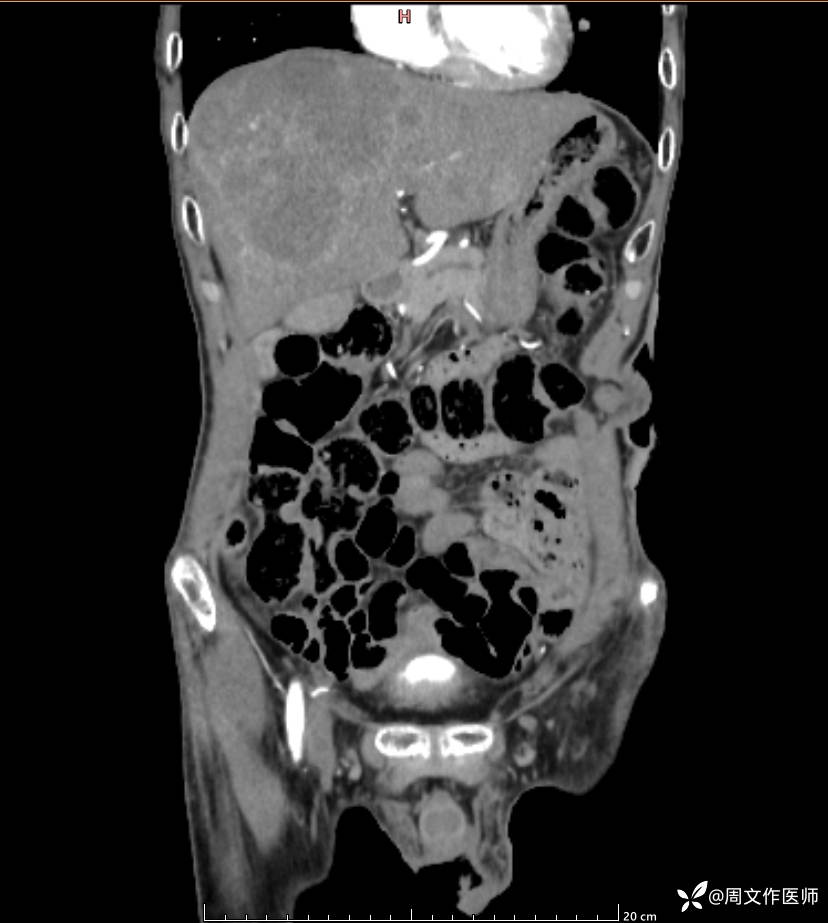

腹部增强CT检查